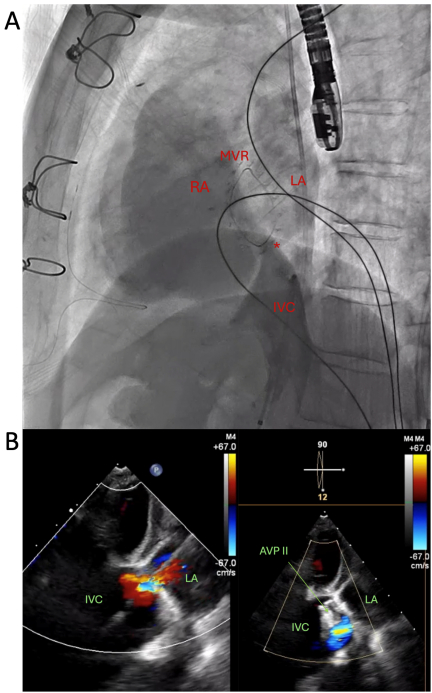

A 67-year-old woman with history of remote surgical atrial septal defect (ASD) repair in childhood and severe mitral regurgitation presented for surgical mitral valve (MV) repair. Pre-operative transesophageal echocardiography (TEE) revealed flail P2 scallop of the MV and no evidence of intracardiac shunt. She underwent redo sternotomy with chordal-sparing bioprosthetic MV replacement on cardiopulmonary bypass (CPB) via femoral cannulation. After coming off CPB, she experienced hypoxemia despite supplemental oxygen. Chest X-ray revealed no acute pulmonary pathology. Initial transthoracic echocardiogram (TTE) showed normal biventricular function, well-seated and normal position and function of the mitral bioprosthesis. TEE showed no evidence of transseptal shunting but revealed a communication between the inferior vena cava (IVC) and left atrium (LA) with continuous right to left shunting (Fig 1). CT angiography of the chest demonstrated an inferoposterior interatrial communication associated with an overriding IVC, consistent with an inferior sinus venosus defect (ISVD) (Fig 2a).

Given patient preference to avoid redo sternotomy, she underwent percutaneous transcatheter closure of the defect using a 12 mm Amplatzer vascular plug (AVP II) with immediate resolution of the hypoxemia following implantation (Fig 3). She returned to her functional baseline with preserved exercise tolerance on follow up with no recurrence of hypoxemia.